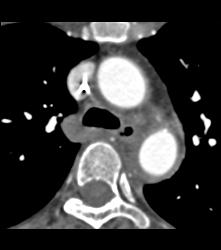

Intramural Hematoma